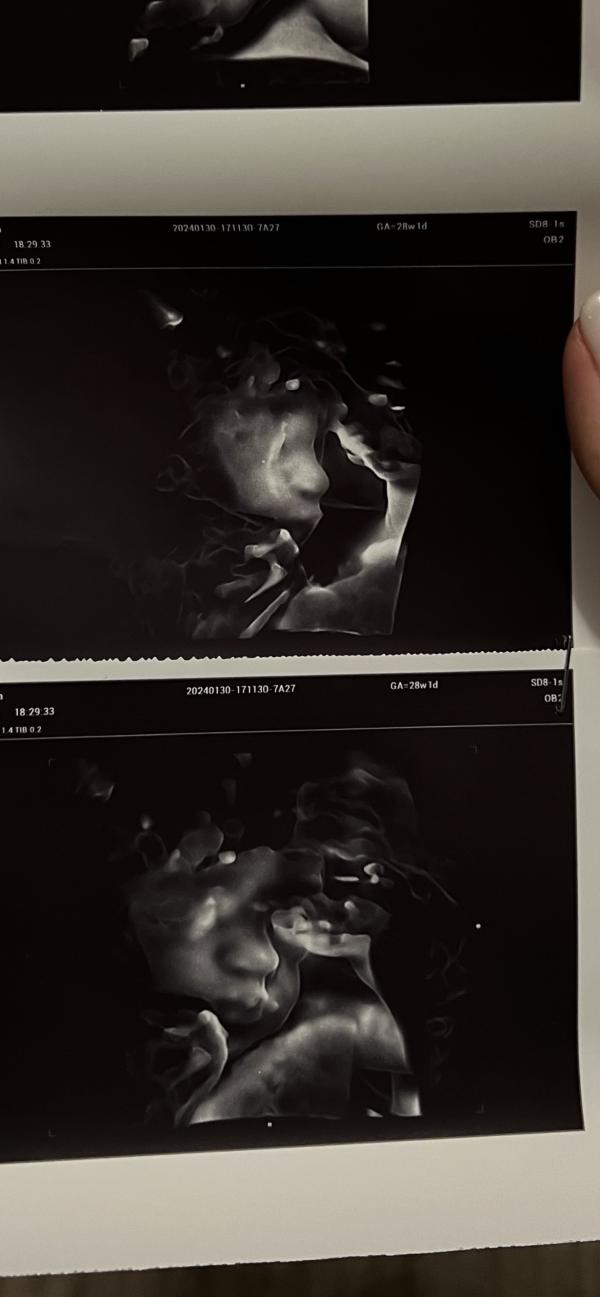

3D УЗИ: это так круто, смотреть на малыша!

так здорово, что сейчас есть возможность делать узи в 3д и смотреть на малыша 🥰